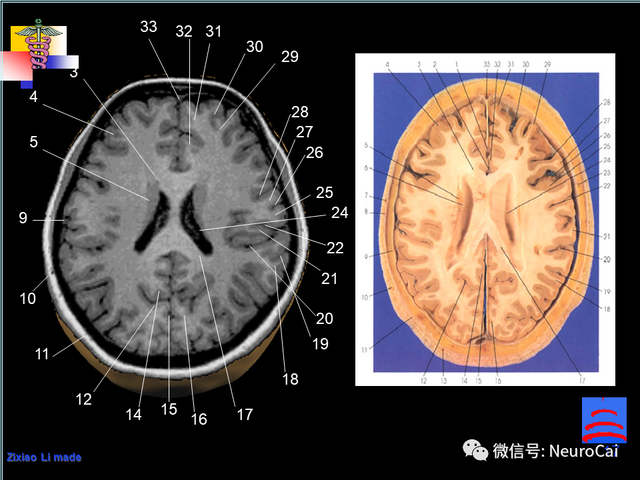

大脑结构图及功能图,人类大脑十大三维解剖图(脑局部解剖与功能图谱)

1、脑局部解剖与功能图谱